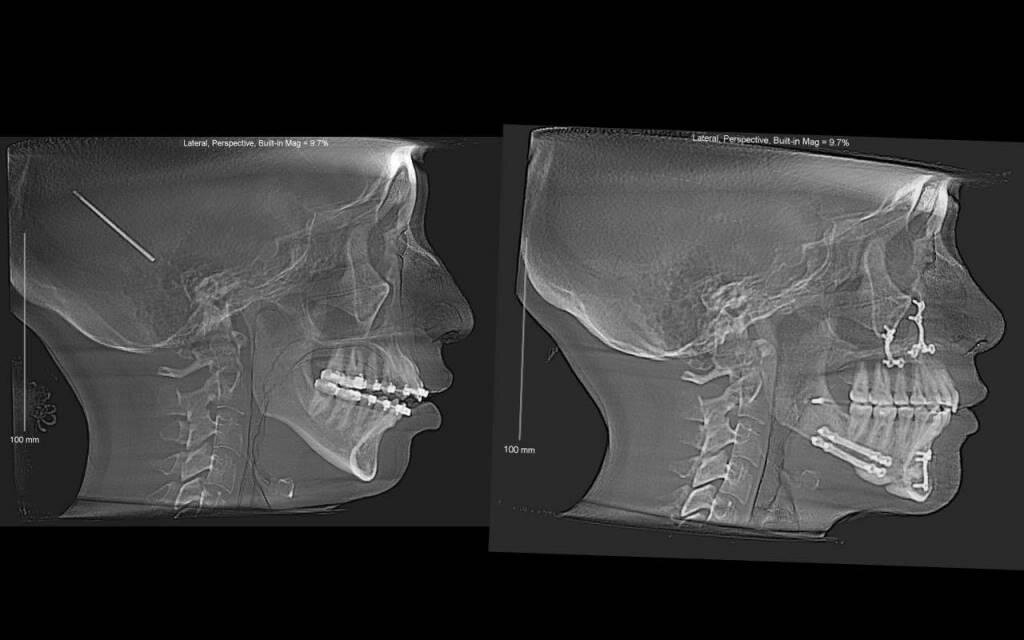

Вчера я была на приёме у стоматолога. Надеялась, что будем лечить верхнюю семёрку. Но, увы, этот зуб возможно придётся удалять. У меня совершенно неправильный прикус - глубокий, да ещё и перекрестный. Это нельзя исправить брекетами и прочими накладками. Здесь нужна операция. Называется она остеотомия нижней челюсти.

Суть её в том, что челюсть "ломают" и ставят на место с помощью титановых пластин. Буду как Терминатор😅

Фото из интернета